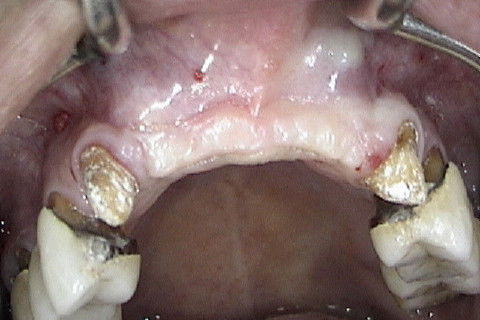

Aspecto clinico da região anterior da maxila 6 meses após o enxerto